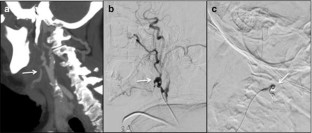

Fig. 3